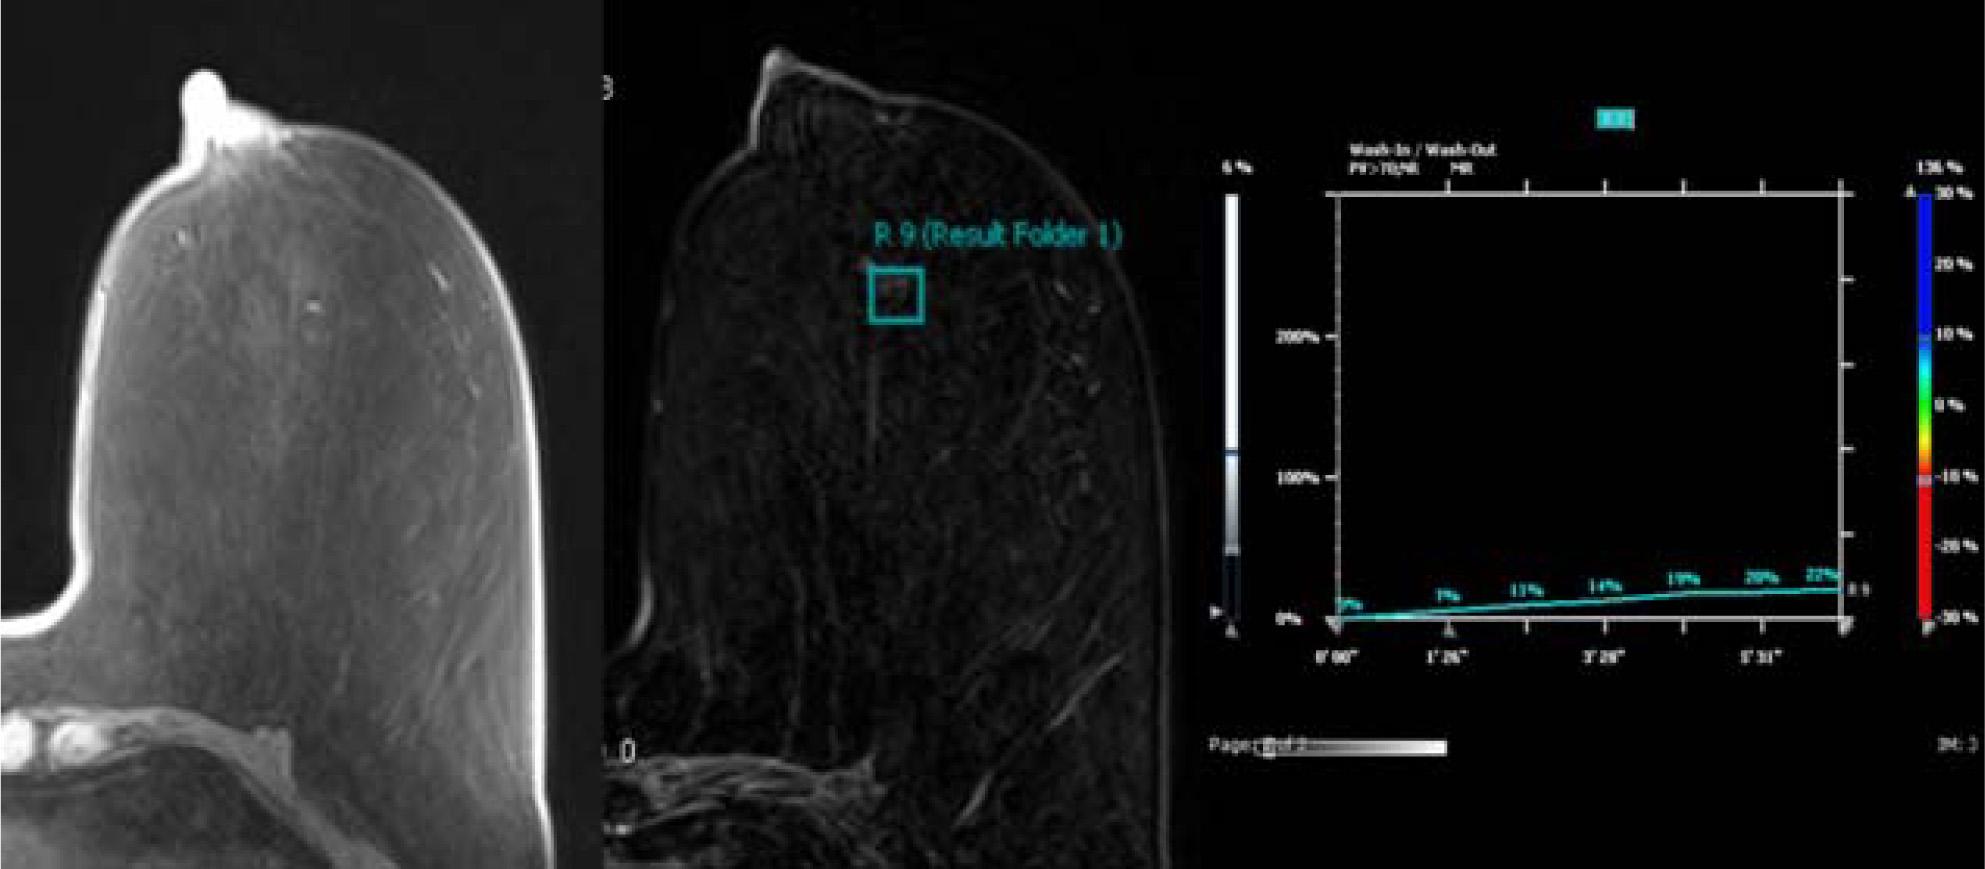

Figure 2